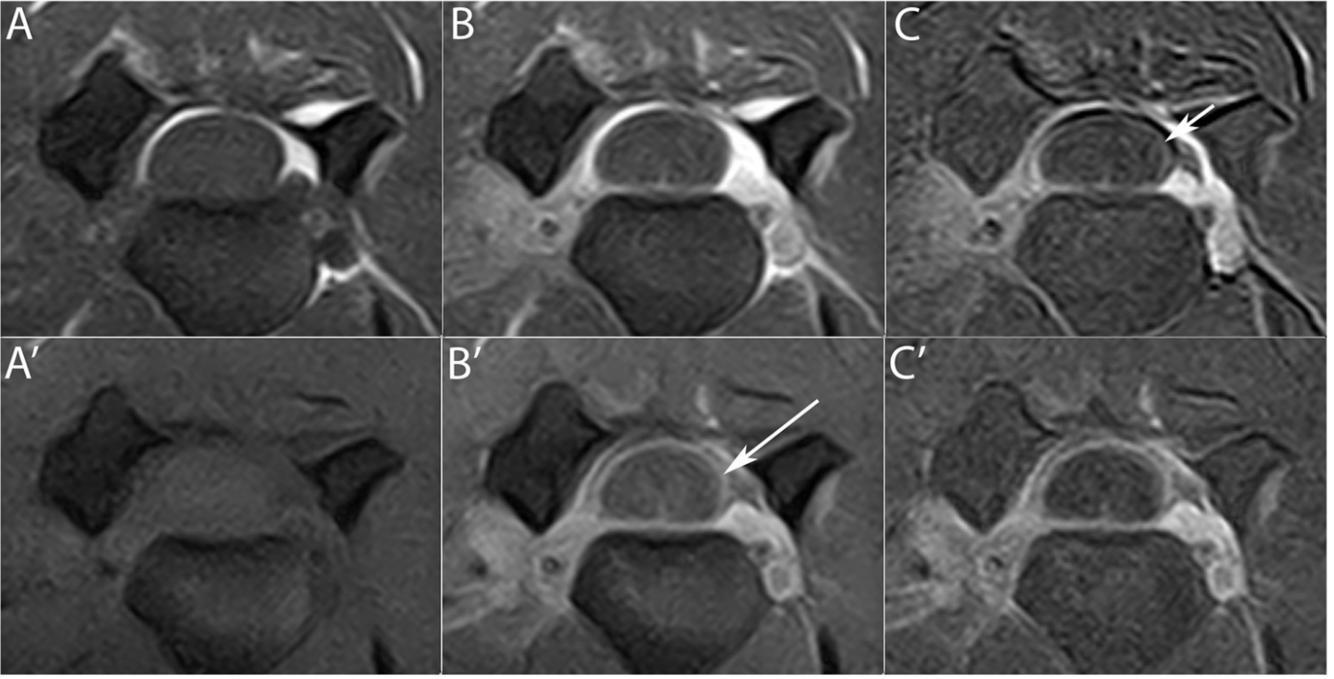

What are the sequences? What is evident?

Transverse T1W (upper row) and T1 FAT SAT (lower row) images pre- (A,A’) and post- (B,B’) contrast administration at the level of the C3–C4 intervertebral space. Meningeal enhancement is visible on the T1W images only with the application of the subtraction technique (C) (short arrow), while it is easily detectable in T1W FAT SAT images (B’) (long arrow). The subtraction technique in T1W FAT SAT images (C’) is therefore not necessary.